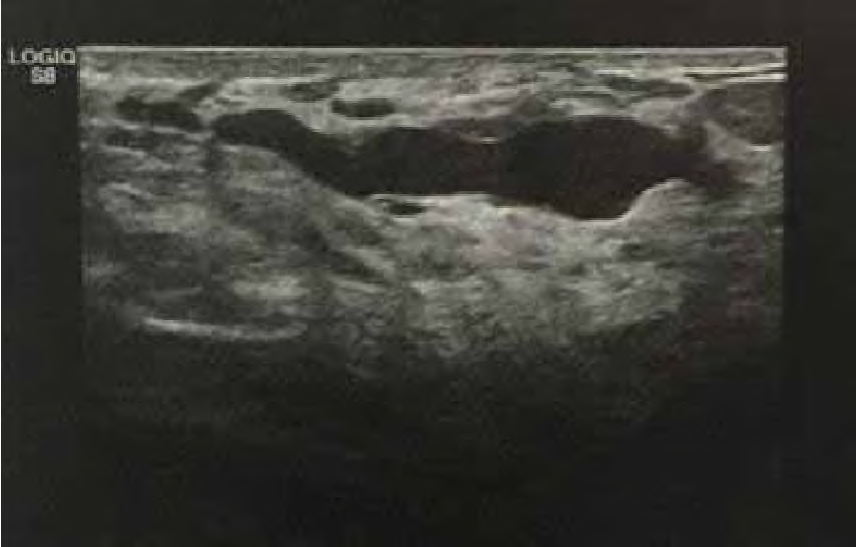

Mulher de 32 anos de idade queixa-se de fluxo papilar à esquerda, de coloração amarelada. Ao exame das mamas, observa-se fluxo papilar, espesso e amarelado, multiductal à expressão. A ultrassonografia é mostrada na imagem.

O diagnóstico é